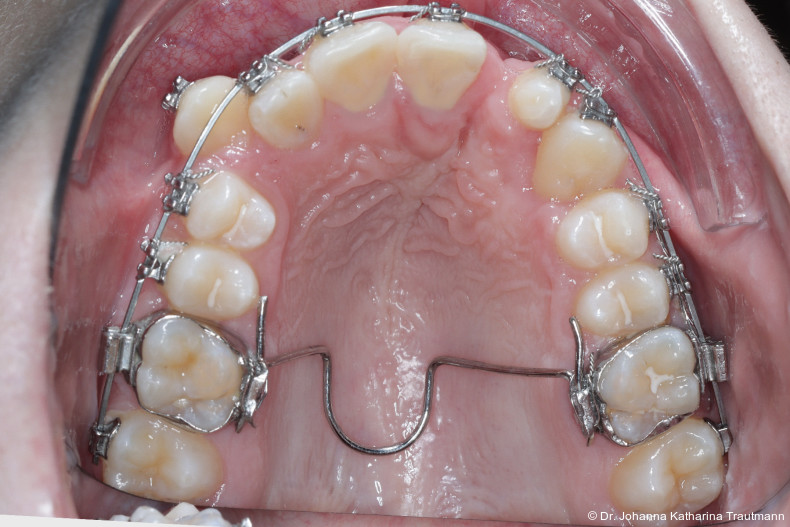

Im Rahmen der Multibrackettherapie wurde bewusst der Zahn 13 aus dem Hauptnivellie rungsbogen ausgelassen, um Kippungen und Asymmetrien im Zahnbogen zu vermeiden. Der Zahn 23 wurde locker mit einer Distanz ligatur angebunden, um eine weitere Bewegung nach vestibulär zu erreichen. Auf einem 0.019" x 0.025" Stahlbogen erfolgte anschlie ßend mittels Umgehungsbiegung sowie eines Overlaybogens (0.014" NiTi) die Integration des Zahnes 13 in den Zahnbogen. Die Zwischendiagnostik nach einem Jahr festsitzender Behandlung zeigte eine gelungene Bisshebung bei guter Nivellierung des Okklusionsplanums und orthoaxialer Einstellung der Frontzähne. Die Zahnbögen präsentierten sich harmonisch ausgeformt, es zeigte sich jedoch eine verbleibende Torqueproblematik an bei den Oberkiefereckzähnen. Nach Freilegung und Einstellung verlagerter Eckzähne ist eine korrekte Torque und Angulationssteuerung häufig eine Herausforderung. Während vestibulär verlagerte Zähne zu gingivalen Rezessionen neigen, behalten palatinal verlagerte Zähne oft ihre palatinale Wurzelstellung bei.13, 14 Die genutzte MBTPrescription der Brackets bietet die Möglichkeit, zwischen +7°, 0° und –7° Torque zu wählen.15 In einem 0.022" System ist bei Verwendung eines 0.019" x 0.025" Bogens jedoch mit einem Torqueverlust von etwa 10° zu rechnen.16

Eine rein klassische „Hochnivellierung“ führt daher zu keiner aus reichenden Torqueübertragung. Alternativ kann ein individualisiert eingebogener Einzelzahntorque eingesetzt werden, um diesen Verlust auszugleichen. Zum Zeitpunkt der Zwischendiagnostik bestand weiterhin eine asymmetrische Bisslage sowie ein vergrößerter Overjet, die beide im weiteren Verlauf mithilfe intermaxillärer Gummizüge korrigiert wurden. Bereits in dieser Phase erfolgte eine Rück sprache mit der Abteilung für Präventive Zahnmedizin, Parodontologie und Kariologie, um eine optimale Ausgangssituation für den späteren odontoplastischen Umbau des Zahnes 22 zu schaffen. Eine präzise kieferorthopädische Einstellung kann die restaurative In vasivität deutlich reduzieren und die Gewebe symmetrie, einschließlich Papillen und Gin giva verlauf, positiv beeinflussen.17, 18 Optimalerweise werden Funktion und Ästhetik vor Entfernung der Multibracketapparatur interdisziplinär abgestimmt, um sowohl aus kieferorthopädischer als auch konservierender Sicht das bestmögliche Ergebnis zu erzielen. Auch das Terminmanagement sollte frühzeitig abgestimmt werden, um eine zügige Rehabilitation zu gewährleisten.

Positiv hervorzuheben ist hingegen der er zielte Knochen erhalt beziehungsweise der partielle Attachmentgewinn im Bereich der Spalte. Wie sich in den Verlaufskontrollen der OPGAufnahmen erkennen lässt, führte die Bewegung der Zähne 21 und 22 in den Spaltbereich zu einer deutlichen Verbesse rung der knöchernen Situation. Obwohl das Knochenniveau nicht vollständig physiologisch ist, konnte ohne zusätzliche Knochenaugmentation eine stabile Knochen und Gewebesituation erreicht werden. Dass ein Attachmentgewinn durch gezielte kieferorthopädische Zahnbewegung möglich ist, wurde bereits von Melsen et al.22 beschrieben. Während sich die meisten nachfolgenden Studien auf parodontal vorgeschädigte Gebisse konzentrierten, zeigt der vorliegende Fall eine mögliche Übertragbarkeit dieser Mechanismen auf Spaltpatienten mit moderatem Knochendefizit.